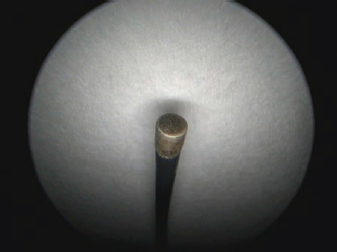

One-and-a-half month after the diagnosis, surgery using monopolar electrocautery was performed. For that, we only needed a semirigid Karl Storz monopolar coagulating ball electrode (3 Fr × 53 cm), LED Surtron 120 high-frequency electrosurgery unit in a monopolar mode, and a grounding steel plate prepared with a thick ultrasonographic gel layer in contact with shaved patient’s skin (Figs. 3-5).

Fig. 5. A semirigid Karl Storz monopolar coagulating ball electrode tip.